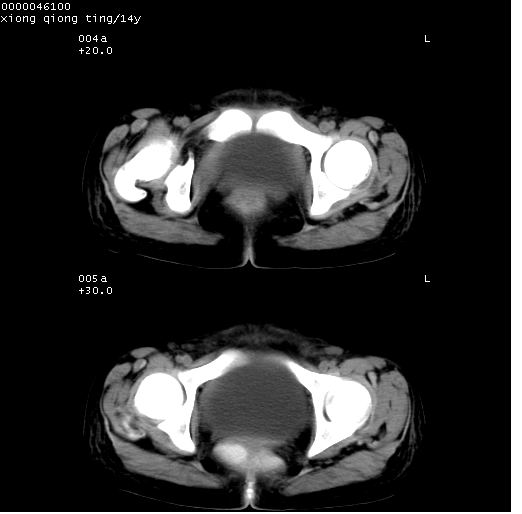

患儿 女,14岁。不规则发热一周,偶感头痛,无抽搐及呕吐。pe:神清,精神差,双侧瞳孔等大等圆,对光反射敏感,双肺未闻及明显啰音,心音有力,腹部触之似揉面感,下腹压痛,无反跳痛。

腹部b超提示:子宫缩小,盆腔积液,肝实质回声密集。

临床诊断:发热原因待查:1)腹部结核感染。2)伤寒?3)结缔组织病?

中下腹及盆腔ct轴位平扫+增强扫描(层厚10mm,螺距1.0,重建间隔10mm),图像如下:

(注:患儿检查当日上午9时口服胃肠道对比剂,下午3时许行ct扫描检查,未行对比剂直肠保留灌肠,检查当日患儿腹泻)

中下腹及盆腔ct轴位扫描(ps+ce)提示:腹部肠管明显充气扩张,并见数个不同宽度之气液平面;疑不全性肠梗阻或肠郁张。临床会诊考虑为患儿腹泻,肠郁张所致;后来未经特殊处理,患儿大便恢复正常,亦无腹胀。

临床出院诊断:1)结核性腹膜炎。2)腹膜后淋巴结结核。3)脂肪肝。